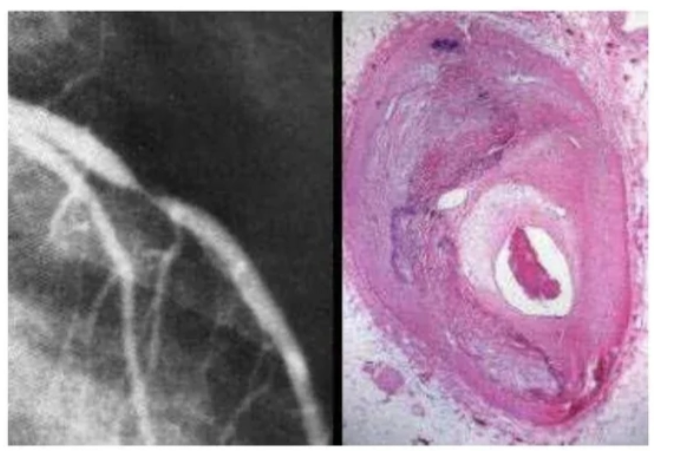

placa de ateroma